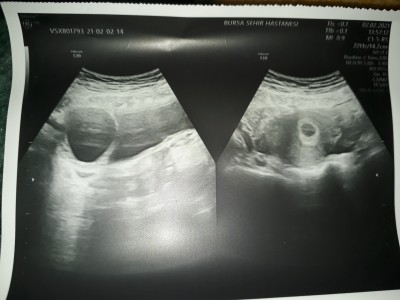

Kızlar ilk kontrolüme gittim kese var bebek yok dedi kese 11 mm mis ama 7 haftaligim haftama göre 11 mm az degilmi 10 gün sonra bidaha çağırdı bide yumurtaligimda kist varmış çok moralim bozuldu :( resim yükledim

Gebelik haftası 7